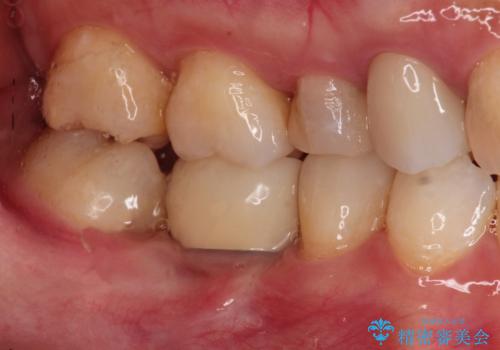

歯並びの改善とインプラントでのかみ合わせの回復 インプラント・セラミック・矯正全顎治療

矯正をはじめ、根の治療・インプラント・セラミックによる全体治療を提案させていただき、治療をしていくこととなりました。

歯医者が怖くて、以前はなかなか通院できなかったが、思い切って治療をしてよかったというお言葉をいただきました。